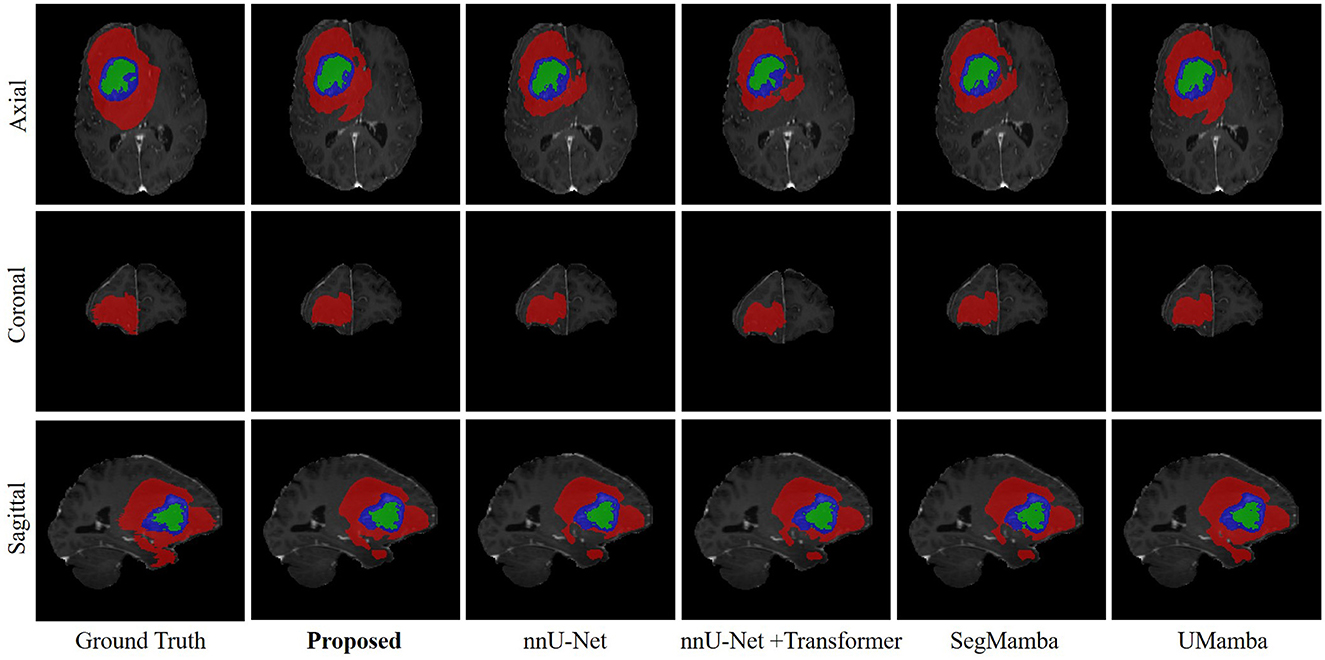

Objectives: Sturge-Weber syndrome (SWS) is a congenital neurological disorder occurring in the early childhood. Timely diagnosis of SWS is essential for proper medical intervention that prevents the development of various neurological issues. Leptomeningeal angiomas (LA) are the clinical manifestation of SWS. Detection of LA is currently performed by manual inspection of the magnetic resonance images (MRI) by experienced neurologist, which is time-consuming and lack of inter-rater consistency. The aim of the present study is to investigate automated LA detection in MRI of SWS patients. Methods: A Mamba-based encoder-decoder architecture was employed in the present study. Particularly, a multi-scale multi-scan strategy was proposed to convert 3-D volume into 1-D sequence, enabling capturing long-range dependency with reduced computation complexity. Our dataset consists of 40 SWS patients with T1-enhanced MRI. The proposed model was first pre-trained on a public brain tumor segmentation (BraTS) dataset and then fine-tuned and tested on the SWS dataset using 5-fold cross validation. Results and Conclusion: Our results show excellent performance of the proposed method, e.g., Dice score of 91.53% and 78.67% for BraTS and SWS, respectively, outperforming several state-of-the-art methods as well as two neurologists. Mamba-based deep learning method can automatically identify LA in MRI images, enabling automated SWS diagnosis in clinical settings.